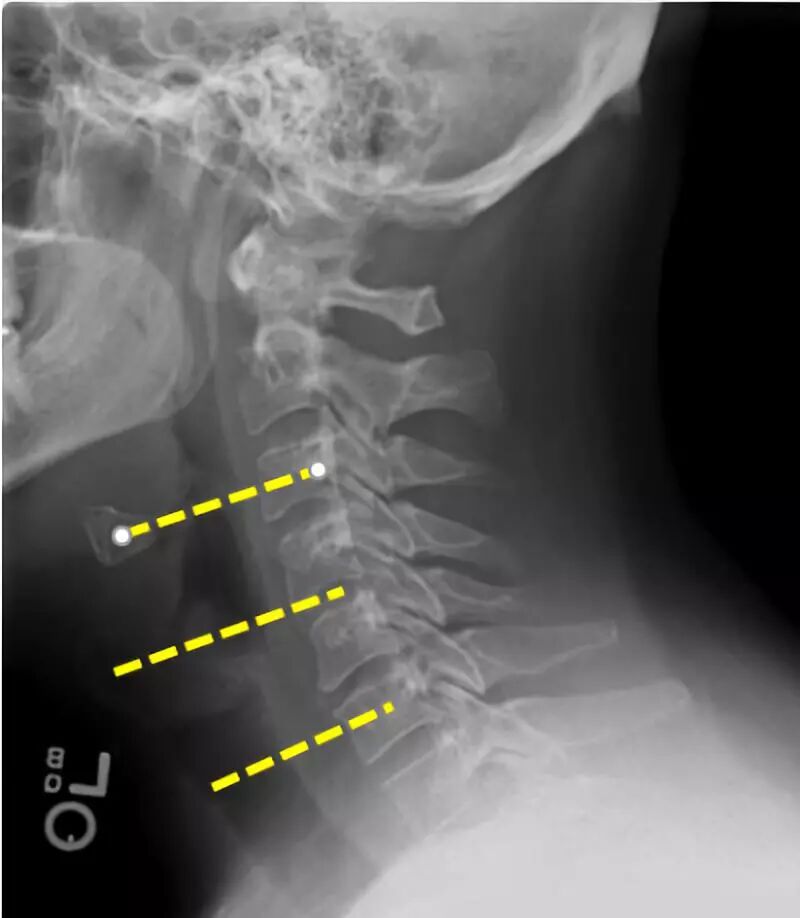

对于单节段ACDF,从胸锁乳突肌(触诊)的中间边缘到中线进行单个水平切口。

确定切口选择的左右侧

右利手的外科医生通常首选右侧切口。

对于左侧切口,左侧喉返神经一般位于气管-食管沟中,理论上不易受伤。

需要考虑的一点是单侧椎间盘骨赘复合体更容易用来自对侧的Kerrison咬骨钳来切除(例如,可以从左侧切口接近右侧椎间盘-骨赘复合体)。

颈椎节段的体表标志:舌骨:C3;甲状软骨:C4-5;颈动脉结节:C6